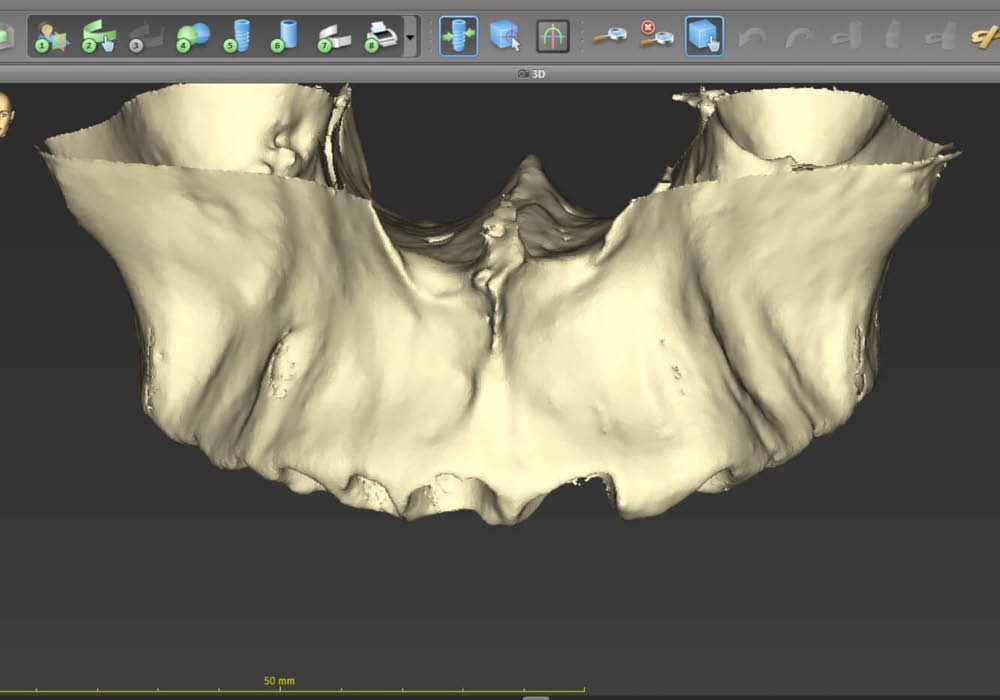

2. Segmentazione DICOM con supporto AI

La segmentazione dei dati CBCT è stata effettuata partendo da un file DICOM.

L’utilizzo dell’intelligenza artificiale ha permesso di automatizzare la separazione e la ricostruzione tridimensionale delle strutture anatomiche, facilitando l’elaborazione e garantendo maggiore precisione nella valutazione iniziale.